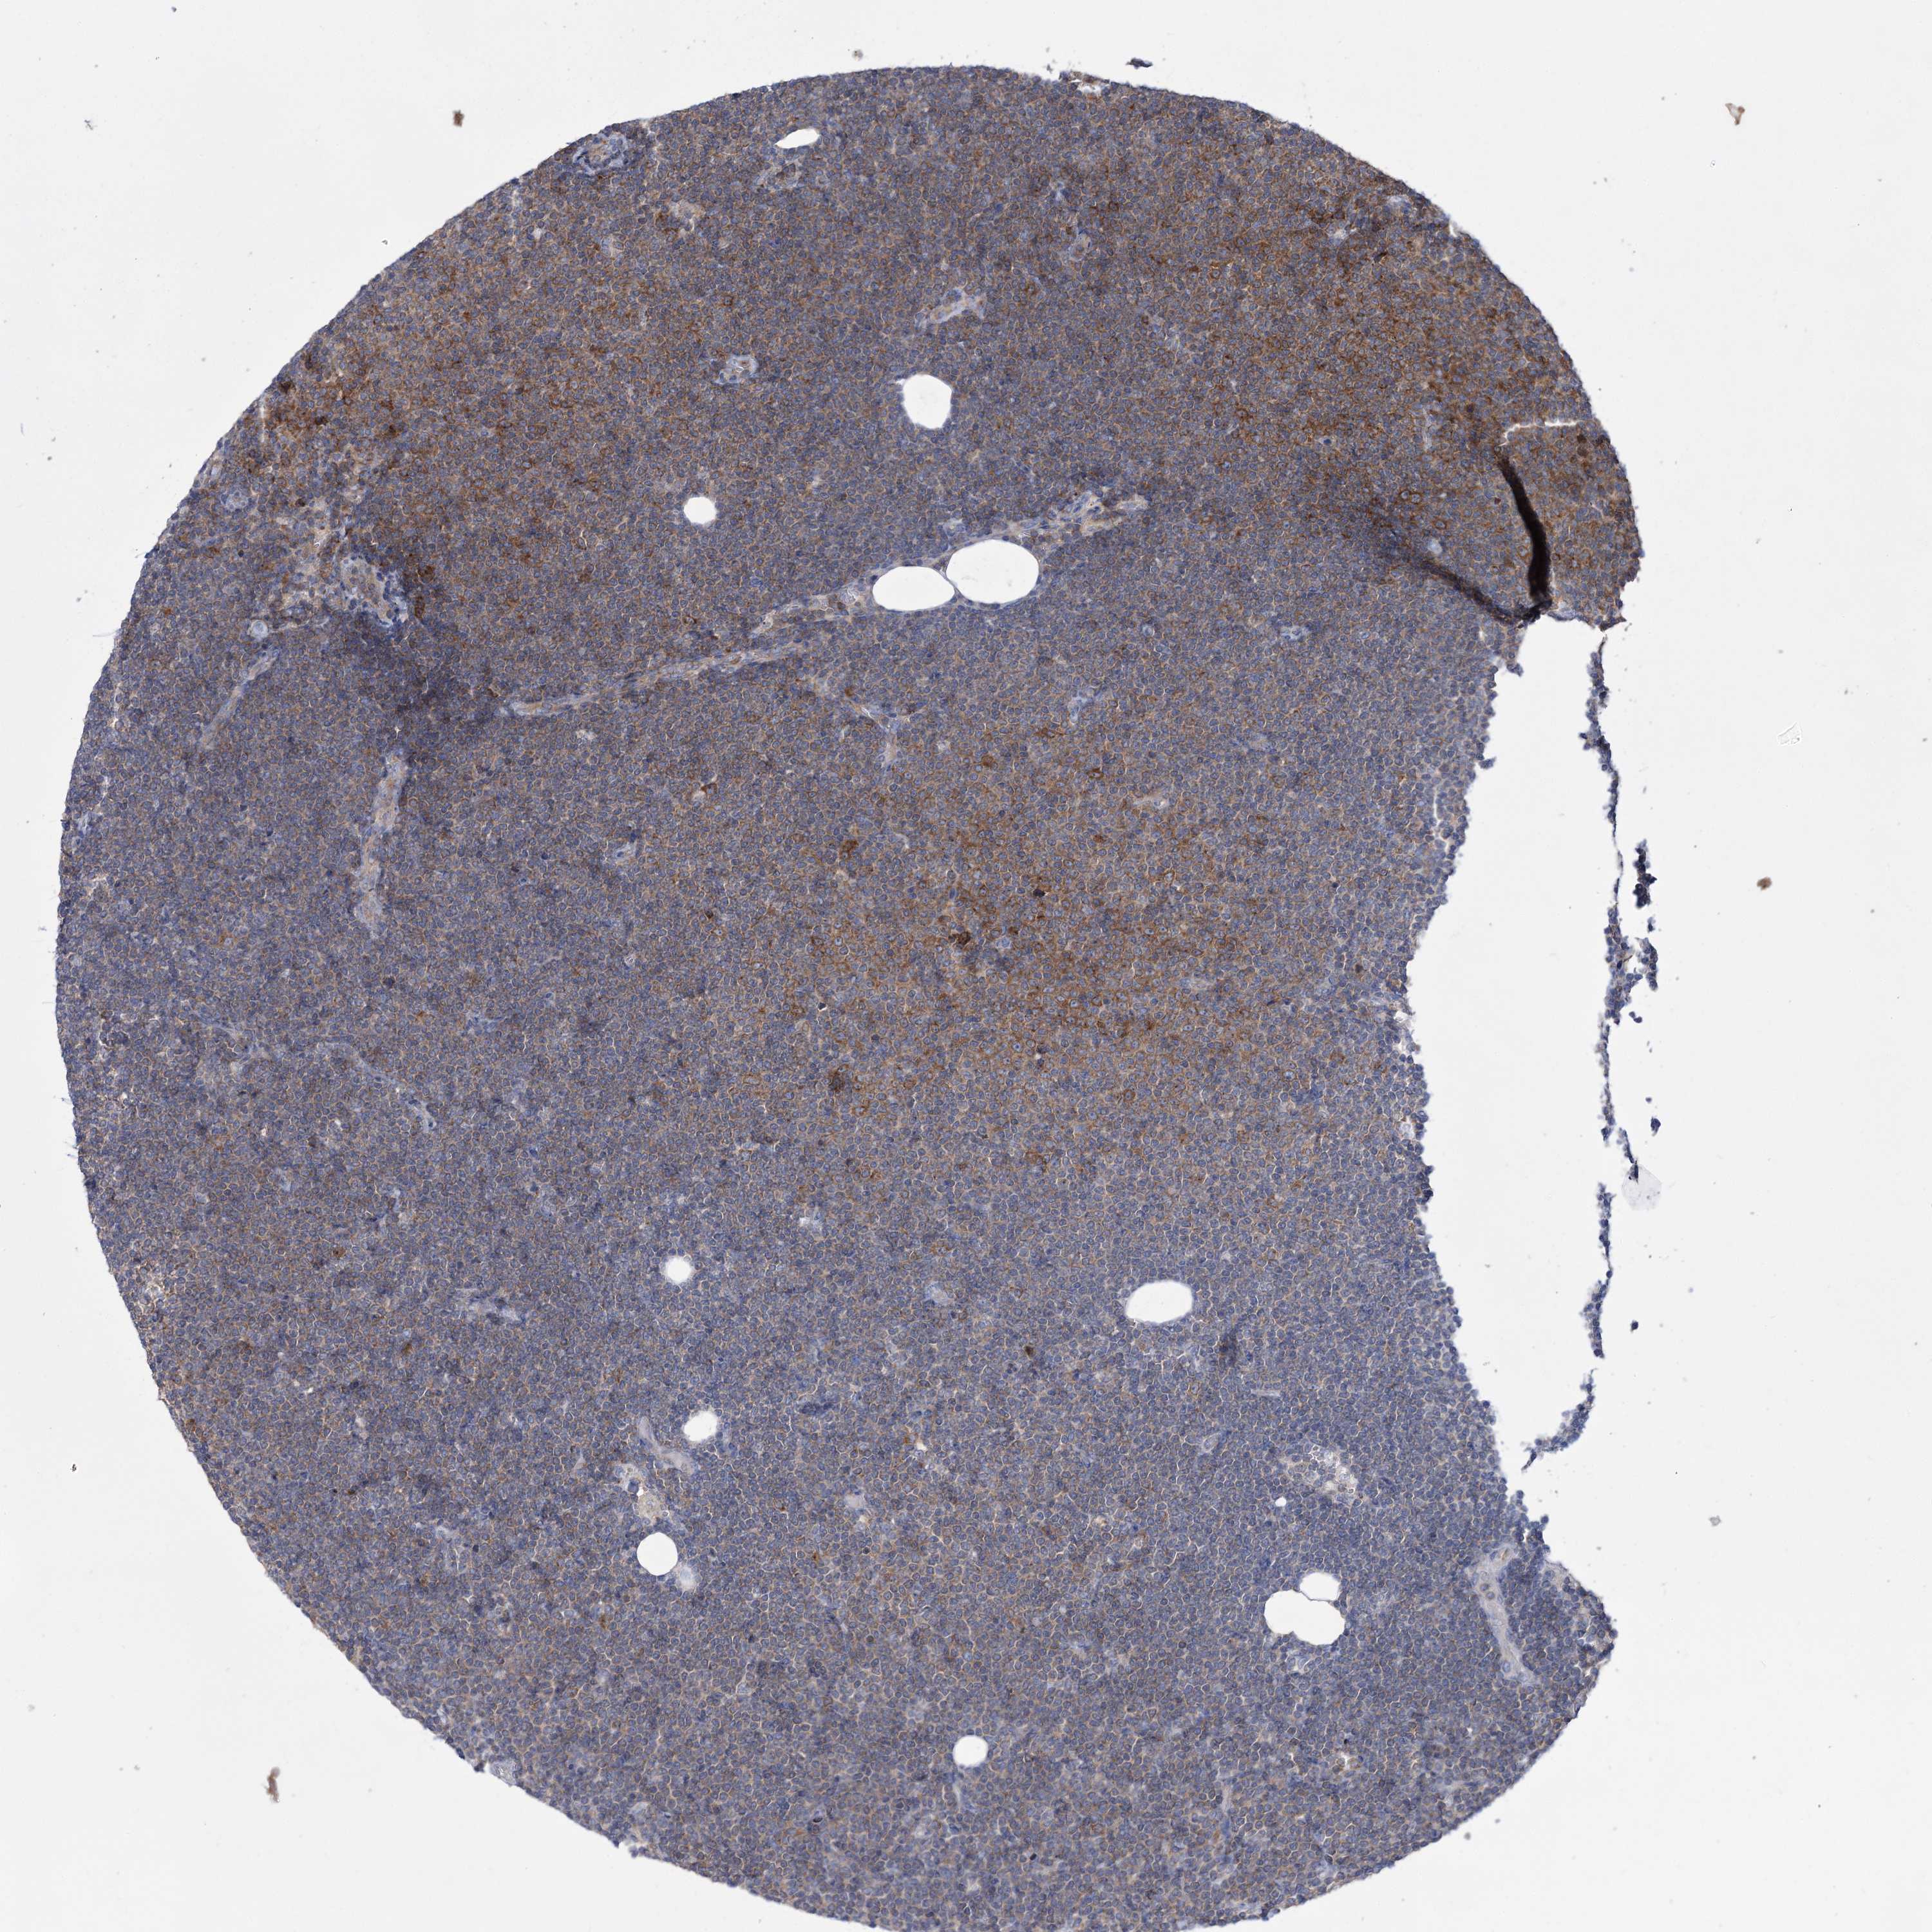

LYMPHOMA - Protein expressioni

A mouse-over function shows sample information and annotation data. Click on an image to view it in a full screen mode. Samples can be filtered based on level of antibody staining by selecting one or several of the following categories: high, medium, low and not detected. The assay and annotation is described here.

Antibody stainingi

Antibody staining in the annotated cell types in the current human tissue is reported as not detected, low, medium, or high, based on conventional immunohistochemistry profiling in selected tissues. This score is based on the combination of the staining intensity and fraction of stained cells.

Each image is clickable and will lead to virtual microscopy that enables deeper exploration of all samples and also displays staining intensity scores, fraction scores and subcellular localization as well as patient and tissue information for each sample.

Antibody HPA036514

Antibody HPA036515

Staining

High

Medium

Low

Not detected

Malignant lymphoma, non-Hodgkin's type, High grade

Malignant lymphoma, non-Hodgkin's type, Low grade

Hodgkin's disease, NOS